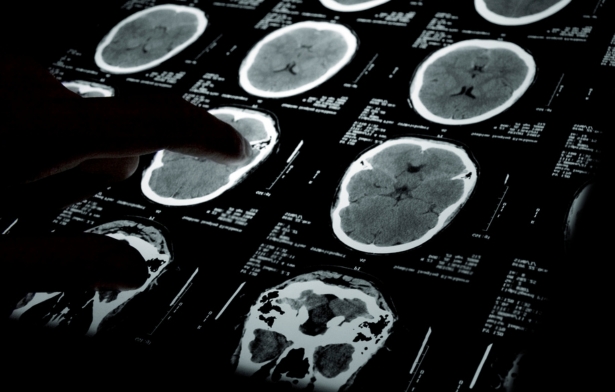

Chụp CT sọ não hay chụp cắt lớp vi tính não là kỹ thuật chẩn đoán hình ảnh không xâm lấn, sử dụng tia X và công nghệ máy tính để tạo ra hình ảnh các lớp cắt ngang của não bộ. Kết quả chụp có thể dựng dưới dạng hai chiều (2D) hoặc ba chiều (3D), hiển thị rõ các chi tiết bên trong hộp sọ, não bộ và các cấu trúc xung quanh. Qua đó, bác sĩ có thể phát hiện các tổn thương, khối u bất thường và chẩn đoán chính xác các bệnh lý liên quan đến vùng đầu (hộp sọ).

Chụp CT sọ não tạo ra hình ảnh chi tiết về cấu trúc và các chi tiết bên trong sọ não